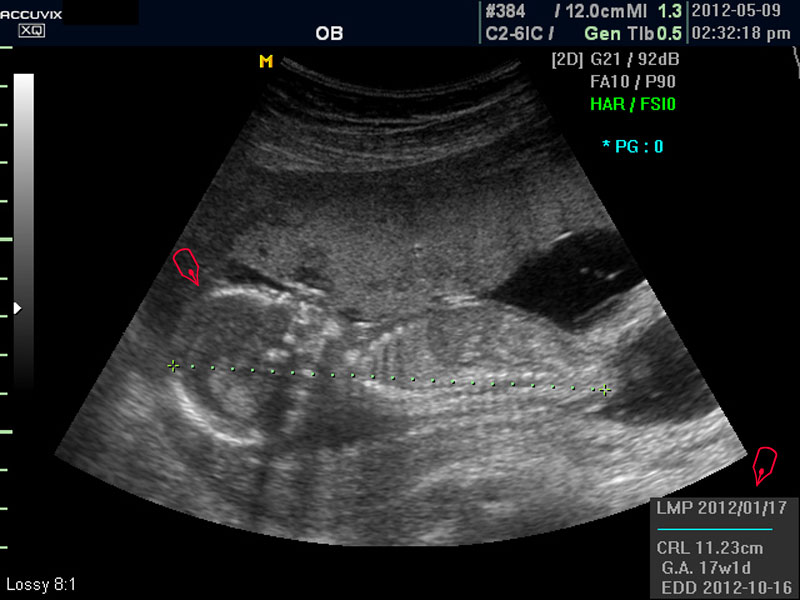

위 사진은 태아의 발바닥 사진인데 사진에서 보는 것처럼 그러나 이 시기는 손가락이나 발가락 또는  심장 내부의 구성 이상 등의 세세한 부분은 아직 크기가 작아서 제대로 확인하기 어려운 시기입니다.

따라서 부분 부분 살펴 보면서 해당 모습을 찍어서 저장하거나 인쇄하여 드리기도 하는 것이며 아래 사진은 태아의 다리 부분을 찍은 것입니다.